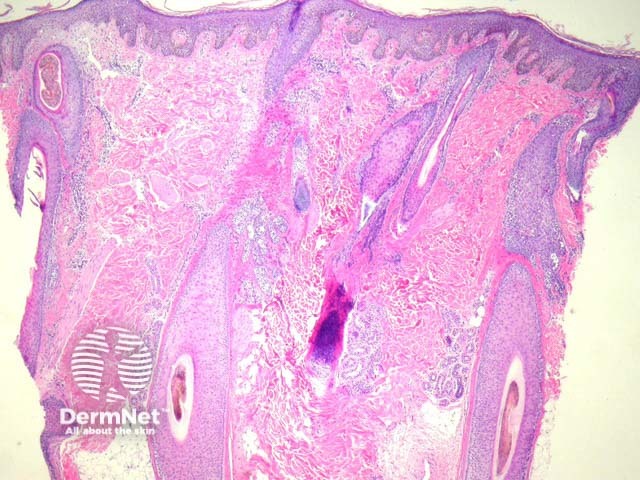

Dermatophytic infections of the scalp (tinea capitis) are characterized by involvement of the hair shaft by pathogenic fungi.

Endothrix infections – There is minimal epidermal response aside from mild hyperkeratosis (figure 1). The hyphae extend within the hair shaft and produce spores (figures 2, 3). This form is caused by Trichophyton tonsurans/violaceum.

Ectothrix infections – There is also often minimal inflammatory reaction. The fungal forms coat the outside of the hair shaft without significant invasion of the shaft itself. This is typically caused by Microsporum canis/audouinii.

Figure 1

The organisms are usually readily seen on high power magnification on haematoxylin-eosin sections (figures 2, 3). GMS and PAS stains can be used to highlight the organisms.

Normal scalp – The fungal organisms may be easily overlooked at low power. There is often minimal inflammatory reaction (figure 1).